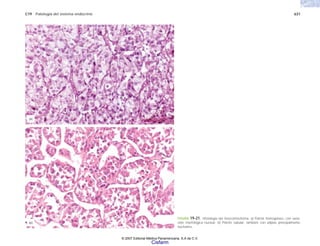

FIGURA 2-7. Mieloma múltiple. a) Histología de la neoplasia. b) Citología de un

frotis del tumor, que permite apreciar la morfología de las células plasmáticas

neoplásicas. (Cortesía del Dr. Joaquín Carrillo.)